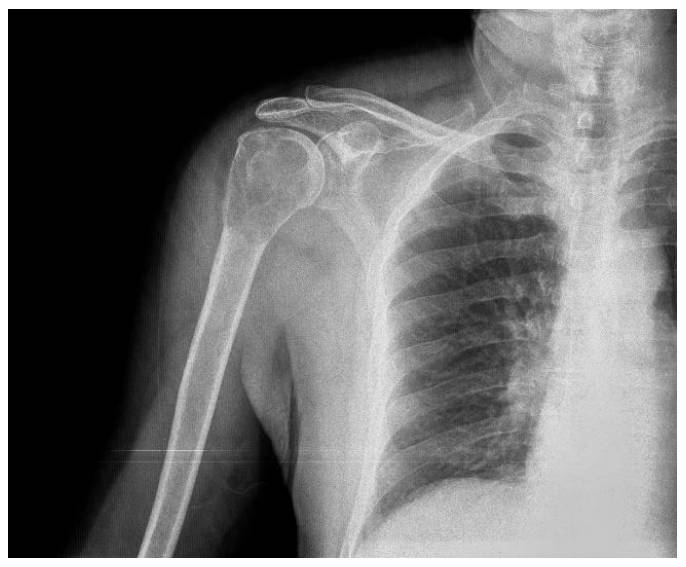

Ameliyat Öncesi: Röntgende proksimal humerus bölgesinde sınırları düzensiz litik lezyon görülmekte